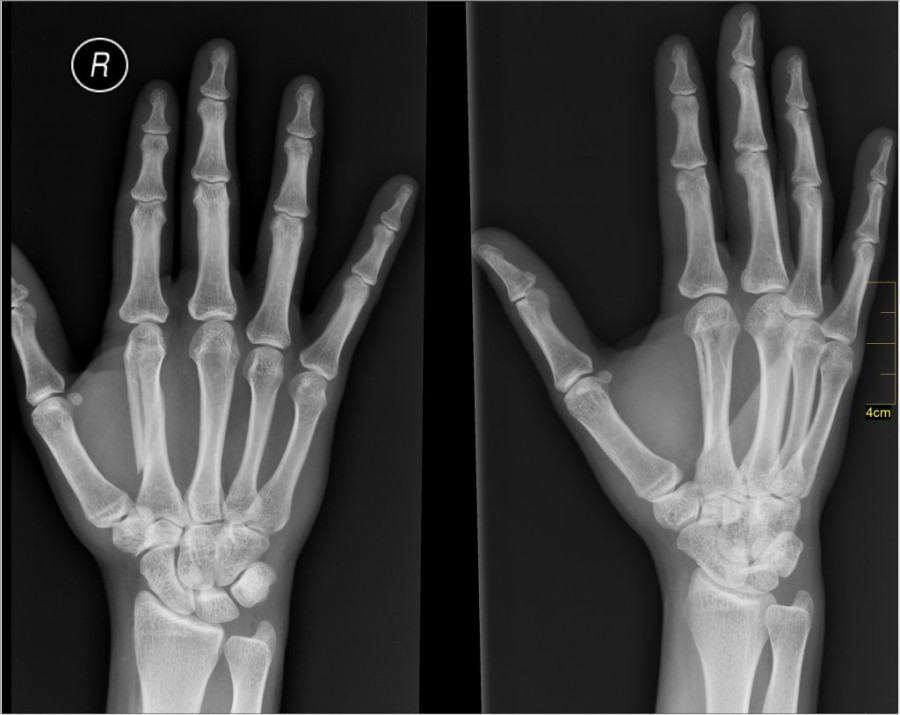

Κάθε τρία δευτερόλεπτα ένα κάταγμα λόγω οστεοπόρωσης, συμβαίνει παγκοσμίως. Υπολογίζεται ότι κάθε χρόνο συμβαίνουν πάνω από 8,9 εκατομμύρια τέτοια κατάγματα, με πάνω από το ένα τρίτο αυτών να συμβαίνει στην Ευρώπη.